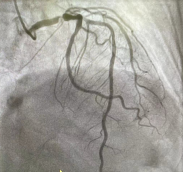

术前冠脉造影图像 术后冠脉造影图像

经过全方位的术前准备后,在心外科、麻醉科、体外循环随时做好抢救性手术的情况下,为患者施行冠脉支架植入术。手术中,心内科Lavarra主任在患者左主干-前降支、回旋支、前降支病变处分别植入1枚支架,整个过程用时80分钟,患者未出现任何不适。术后患者的胸痛症状得到缓解,于3日后出院。